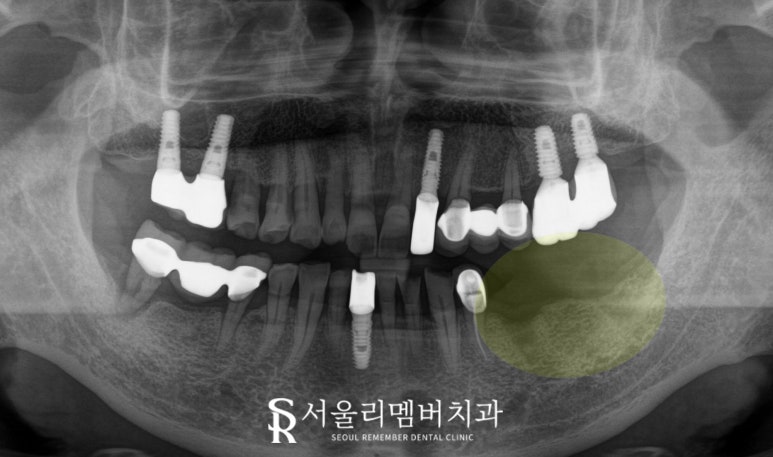

구강 사진을 보면

왼쪽 아래 구치부가 없습니다.

두 번째 작은 어금니(제2소구치)부터

두 번째 큰 어금니(제2대구치)까지

총 3개가 부족한 상황으로

언제부터 이가 없었는지

정확한 시기는 알 수 없으나

빠진지 꽤 오랜 시간이 지나

현재 상도동 치과 에서 보기에

치조골이 굉장히 얇아 보입니다.

치아가 존재하지 않으니

그 자리의 뼈가 흡수되고

퇴축하면서 이렇게 점차

얇아지게 된 것이죠.

또한 원래 위아래가 고르게 맞물려야 되는데

한쪽이 없다면

나머지 한쪽에 정출되는 현상이 발생하는데,

이 케이스에서는 다행(?)스럽게도

상악 대합치가 임플란트라서

이가 움직이진 않을 것 같습니다.